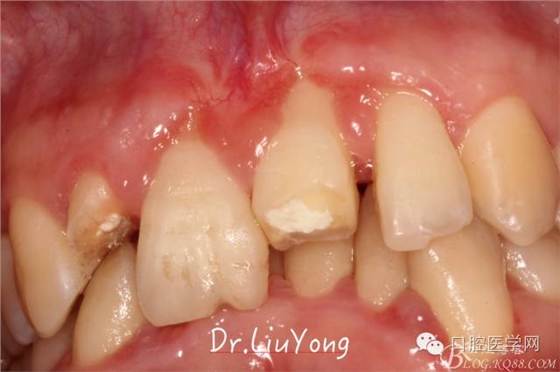

檢查:面部對(duì)稱無(wú)腫脹畸形,張口度正常,口內(nèi)檢查可見(jiàn)A2牙冠缺失,可見(jiàn)直徑約1.5mm左右穿髓孔,冷熱刺激痛+,叩痛+,探痛+,近中斷面探診位于齦下1.5mm,A1B1B2松動(dòng)2-3度,B1牙冠缺失1/2,冷熱刺激痛-,叩痛+,B2牙冠完整,A2-B2牙齦紅腫,探診極易出血,全口口腔衛(wèi)生差,牙結(jié)石++,A1B1之間牙齦乳頭紅腫嚴(yán)重,B1唇側(cè)牙齦萎縮明顯,牙齦邊緣可見(jiàn)縫線兩處,局部有滲出,齦緣冠方1mm處見(jiàn)白色骨塊,松動(dòng),觸痛明顯,觸及骨塊時(shí)可見(jiàn)B1及B2近中唇側(cè)牙齦動(dòng)度,B1B2之間唇側(cè)牙齦乳頭缺失,B2近中根面可見(jiàn)大量牙結(jié)石。重度深覆合,牙尖交錯(cuò)位時(shí)C3-D2咬至上前牙腭側(cè)齦緣,A1切端咬至C12唇側(cè)齦緣。其余牙齒未見(jiàn)明顯異常。

術(shù)前口內(nèi)照片如下: